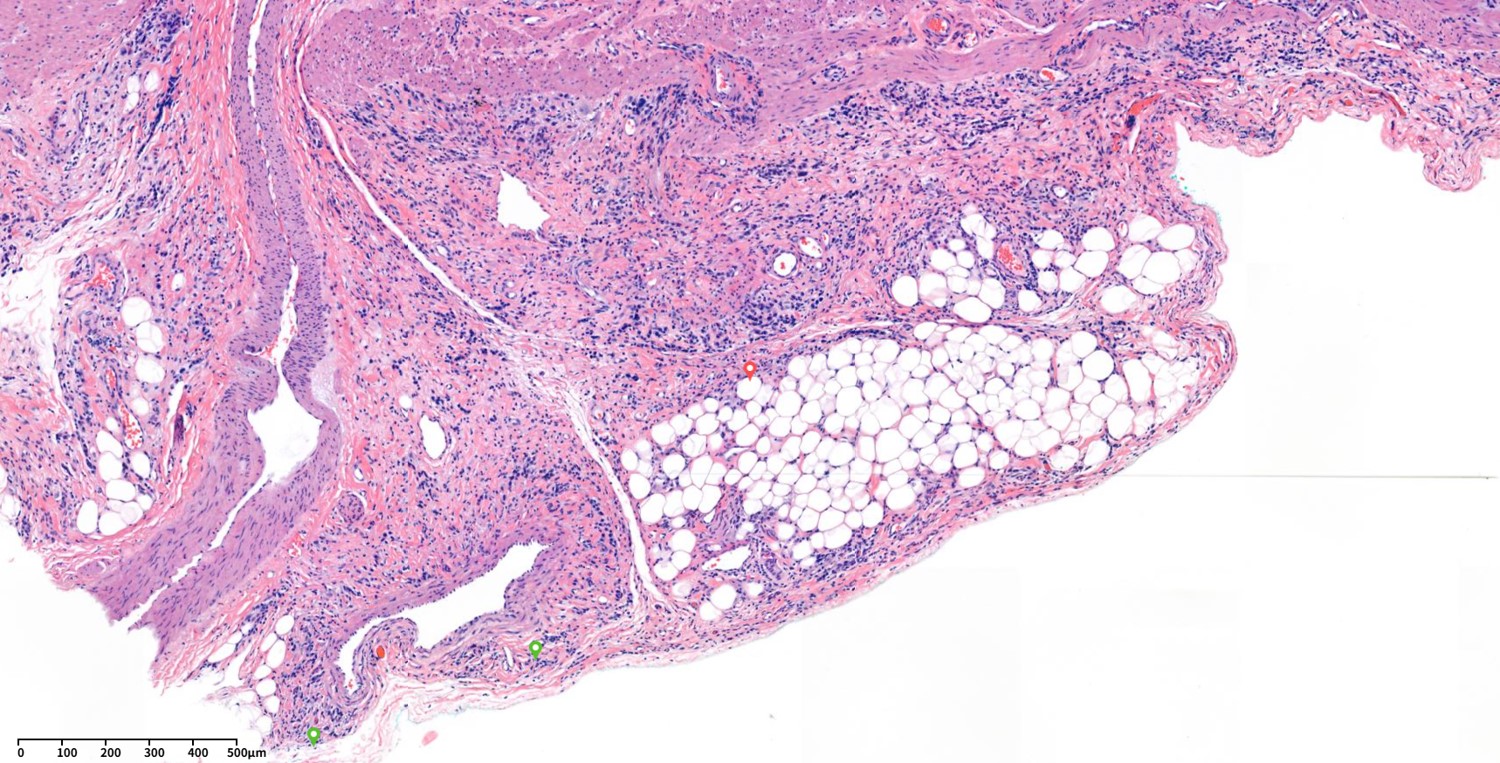

This is a typical case with AGC with serosal invasion.

Serosal invasion is T4a.